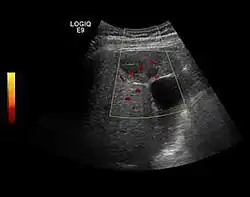

US examination is required to detect liver metastases in patients with oncologic history. In addition, the method can incidentally detect metastases in asymptomatic patients. Early identification (small sizes, small number) is important to establish an optimal course of treatment which can be complex (chemotherapy, radiofrequency ablation, surgical resection) but welcomed. In addition, discrimination of synchronous lesions that have a different nature is also important knowing that up to 25–50% of liver lesions less than 2 cm detected in cancer patients may be benign . US sensitivity for metastases detection varies depending on the examiner's experience and the equipment used and ranges between 40 and 80% . Sensitivity is conditioned by the size and acoustic impedance of the nodules. For a lesion diameter below 10 mm US accuracy is greatly reduced, reaching approx. 20%. Other elements contributing to lower US performance are: excessive obesity, fatty liver disease, hypomobility of the diaphragm, and certain patterns of hyperechoic or isoechoic metastases that can be overlooked or can mimic benign conditions. Conventional US appearance of metastases is uncharacteristic, consisting of circumscribed lesions, with clear, imprecise or "halo" delineation, with homogeneous or heterogeneous echo pattern. They can be single (often liver metastases from colonic neoplasm) or multiple. Echogenity is variable. When increased, they can compress the bile ducts (which may be dilated) and the liver vessels. Liver involvement can be segmental, lobar or generalized. In this situation a pronounced hepatomegaly occurs. Generally, metastases have non-characteristic Doppler vascular pattern, with few exceptions (carcinoid metastases). Cyst-adenocarcinoma metastases due to semifluid content may have a transonic appearance. When increasing, they can result in central necrosis. CEUS examination is a real breakthrough for detection and characterization of liver metastases.

Increased performance is based on identifying specific vascular patterns during the arterial phase and seeing metastases in contrast to normal liver parenchyma during the sinusoidal phase. CEUS increased accuracy is due to the different behavior of normal liver parenchyma (captures CA in Kuppfer cells) against tumor parenchyma (does not contain Kuppfer cells, therefore CEUS appearance is hypoechoic). To this adds the particularities of intratumoral circulation represented by a reduced arterial bed compared to that of the surrounding normal liver and the absence of the portal vessels . In terms of vascularity, metastases can be hypovascular (in gastric, colonic, pancreatic or ovarian adenocarcinomas) with hypoechoic pattern during arterial phase, and similar during portal venous and late phases, respectively hypervascular (neuroendocrine tumors, malignant melanoma, sarcomas, renal, breast or thyroid tumors) with hyperechoic appearance during arterial phase, with washout during the portal venous phase and hypoechoic pattern 30 seconds after injection.